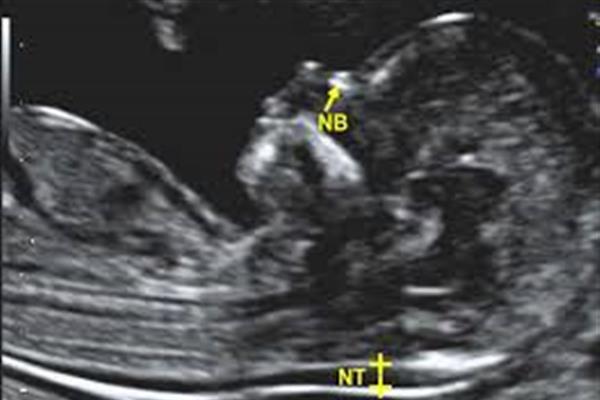

سونوگرافی غربالگری NT در بارداری یکی از مهمترین آزمایشها در دوران بارداری است که به ارزیابی احتمال برخی ناهنجاریهای کروموزومی، از جمله سندرم داون، کمک میکند. در این مقاله، اهمیت سونوگرافی NT، زمان ایدهآل برای انجام آن و نکات کلیدی برای افزایش دقت نتایج این آزمایش را بررسی میکنیم.

سونوگرافی NT که به عنوان سونوگرافی شفافیت پشت گردن نیز شناخته میشود، به پزشک این امکان را میدهد تا ضخامت مایع تجمعیافته در پشت گردن جنین را اندازهگیری کند. این آزمایش در هفتههای ۱۱ تا ۱۴ بارداری انجام میشود و ضخامت غیرطبیعی میتواند نشانهای از برخی مشکلات کروموزومی باشد.

زمان مناسب برای انجام سونوگرافی NT در هفته ۱۲ بارداری است، زیرا در این زمان وضوح تصویر بهتر بوده و اندازهگیری ضخامت NT دقیقتر انجام میشود. تجربه نشان داده که انجام این آزمایش در حوالی هفته ۱۲ نتایج مطلوبتری ارائه میدهد.

این آزمایش برای تشخیص زودهنگام برخی مشکلات کروموزومی و ناهنجاریهای جنینی بسیار حائز اهمیت است. اهداف اصلی سونوگرافی NT عبارتند از: